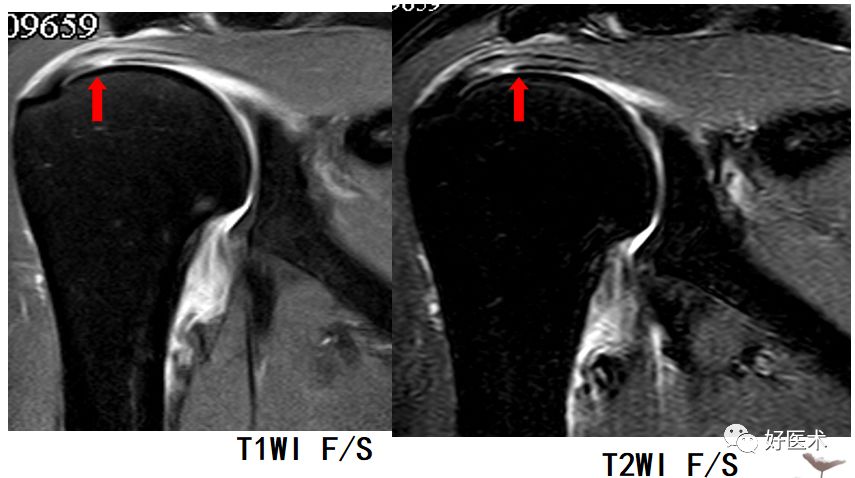

骨结构改变

-

主要为肩峰退行性病变:T1WI及T2WI见低信号的骨赘影

冈上肌完全撕裂

冈上肌全层撕裂伴肩撞(骨赘形成)